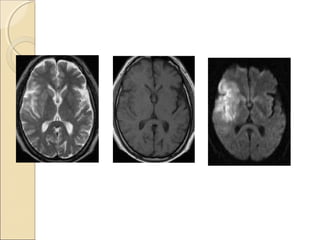

T2 W

FLAIR